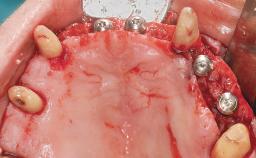

Immediate Loading of Six Implants in the Maxilla and Final Restoration with a Full-Arch CAD/CAM Zirconia FDP

A 63-year-old male patient was referred for a consultation and treatment of partial edentulism in the maxilla. The patient presented with residual anterior teeth and declined a partial removable prosthesis. He reported that the maxillary posterior teeth had been extracted due to mobility and periodontal disease two months before the consultation. The patient’s chief complaint was that his residual maxillary teeth were mobile and that he was unable to chew. The patient’s desire was a stable and comfortable fixed maxillary rehabilitation. The patient was a light smoker (fewer than 10 cigarettes/ day), and his medical history was without significant findings. He was not on any regular medication at the time of consultation. The extraoral examination revealed a normal physiognomy with a correct distribution of the facial thirds. The patient presented a low lip line, and the transition line between teeth and soft tissues was not exposed during a forced smile.

# of Implants 6

Bone Augmentation Horizontal|Simultaneous